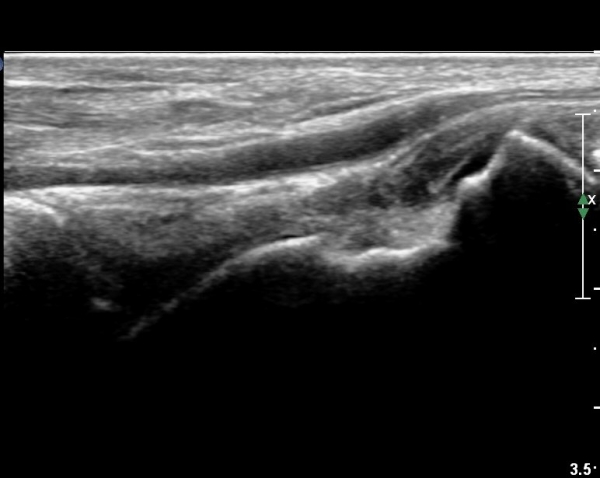

¹ß¸ñ ¾ÕÂÊ Á¾´Ü¸é°Ë»ç¿¡¼­ ¹ß¸ñ°üÀý³» °æ¹ÌÇÑ ¼ö¾×Àú·ù¸¦ º¸À̰í(»çÁø 1, 2)

°Å°ñÁÖ»ó°ñ°üÀýÀÇ ¼ö¾×Àú·ù°¡ °üÂûµÈ´Ù(»çÁø 3).